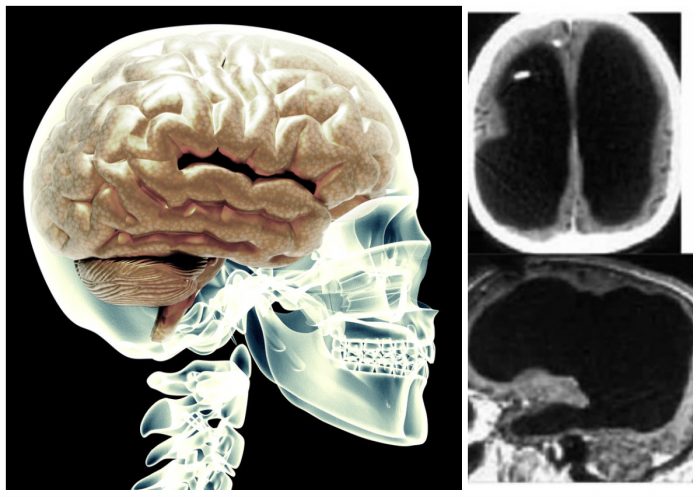

Ο άνδρας αυτός ζούσε με σχεδόν 5% του εγκεφάλου του ενώ το υπόλοιπο 95% είχε υποχωρήσει.

Το κενό μέρος του κρανίου του είχε γεμίσει με υγρό το οποίο είχε συσσωρευτεί από τα παιδικά του χρόνια.

«Είναι δύσκολο να πω το ακριβές ποσοστό έλλειψης εγκεφάλου, εφόσον δεν χρησιμοποιήσαμε λογισμικό για να μετρήσουμε τον όγκο. Αλλά οπτικά δείχνει από 50% έως 75% ή και παραπάνω», δήλωσε ο νευρολόγος του Μεσογειακού Πανεπιστημίου της Μασσαλίας, Λάιονελ Φογέτ.

Συγκεκριμένα, από τον ασθενή έλειπαν οι περιοχές του εγκεφάλου που είναι υπεύθυνες για την κίνηση, την όραση, την ομιλία, τις συναισθηματικές και διανοητικές λειτουργίες καθώς και την ευαισθησία.

Στην ηλικία των έξι μηνών έπασχε από υδροκεφαλία και του εμφύτευσαν βαλβίδα στον εγκέφαλο για να αδειάζει το υγρό.

Στην ηλικία των δεκατεσσάρων άρχισε να εμφανίζει συμπτώματα πάρεσης στο αριστερό του πόδι και έτσι του αφαίρεσαν την βαλβίδα.

Έκτοτε, το υγρό που συσσωρευόταν στο κεφάλι του άρχισε σταδιακά να καταστρέφει τον εγκέφαλό του.